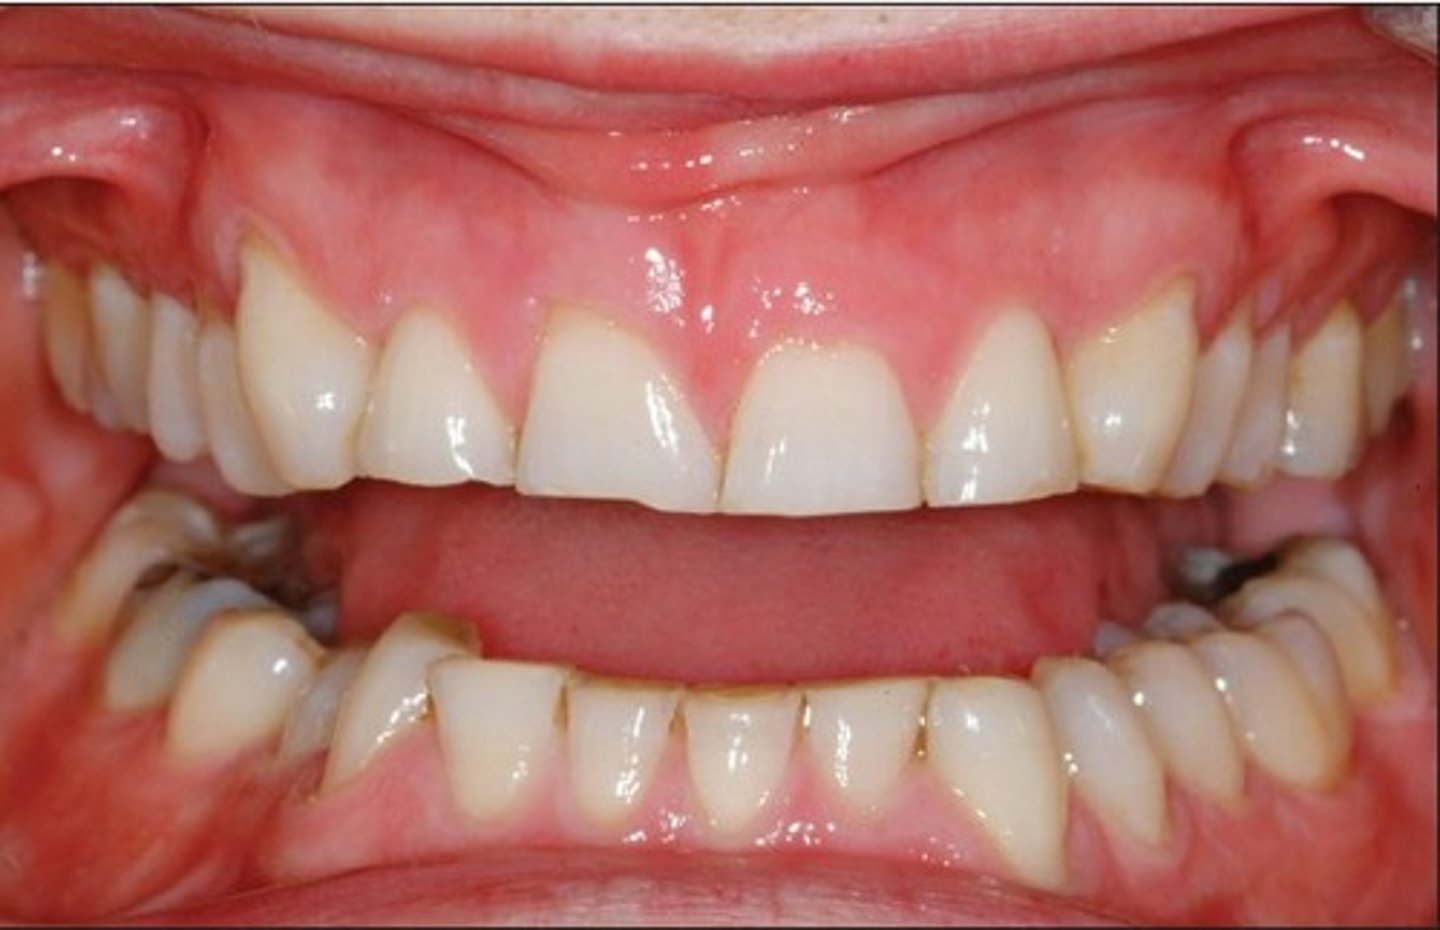

edge to edge

What is this called for the anterior teeth?

<p>What is this called for the anterior teeth?</p>